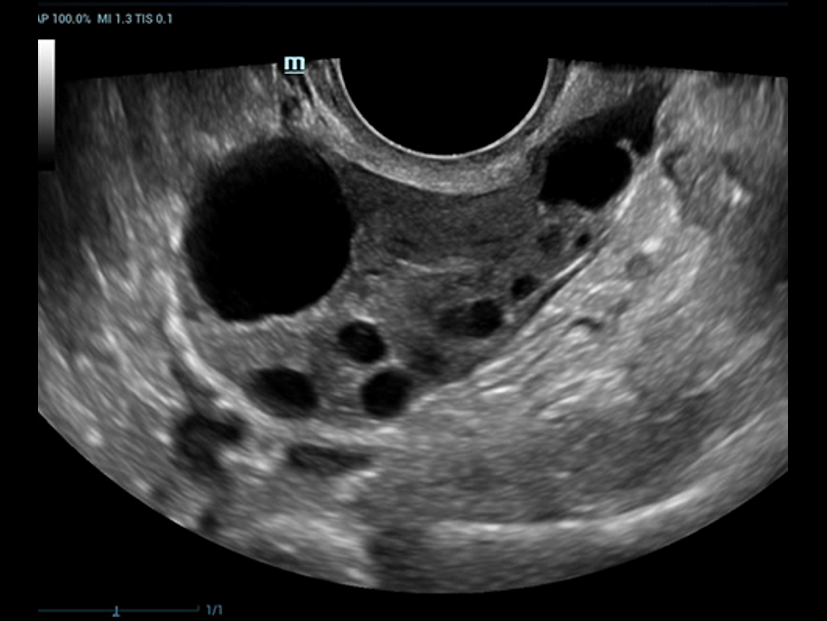

Fin dalla sua fondazione Mindray esplora continuamente nuovi modi per migliorare l'affidabilit├Ā diagnostica. Equipaggiata con la pi├╣ rivoluzionaria tecnologia ZONE Sonography?, la nuova piattaforma ZST+ di Resona 7 porta la qualit├Ā dell'immagine ecografica ad un livello superiore con l'acquisizione per zone e l'elaborazione dei dati canale.

Oltre alla qualit├Ā delle immagini di livello eccellente, Resona 7 migliora anche le capacit├Ā di ricerca clinica il rivoluzionario V Flow per la valutazione emodinamica vascolare, e l'acquisizione piani pi├╣ intelligente dal set di dati 3D per la diagnosi del sistema nervoso centrale fetale. Combinando il pi├╣ intuitivo funzionamento multi-touch basato su gesti e tutte le caratteristiche cliniche essenziali, Resona 7 sta veramente portando nuove tendenze nellŌĆÖinnovazione dellŌĆÖecografia.